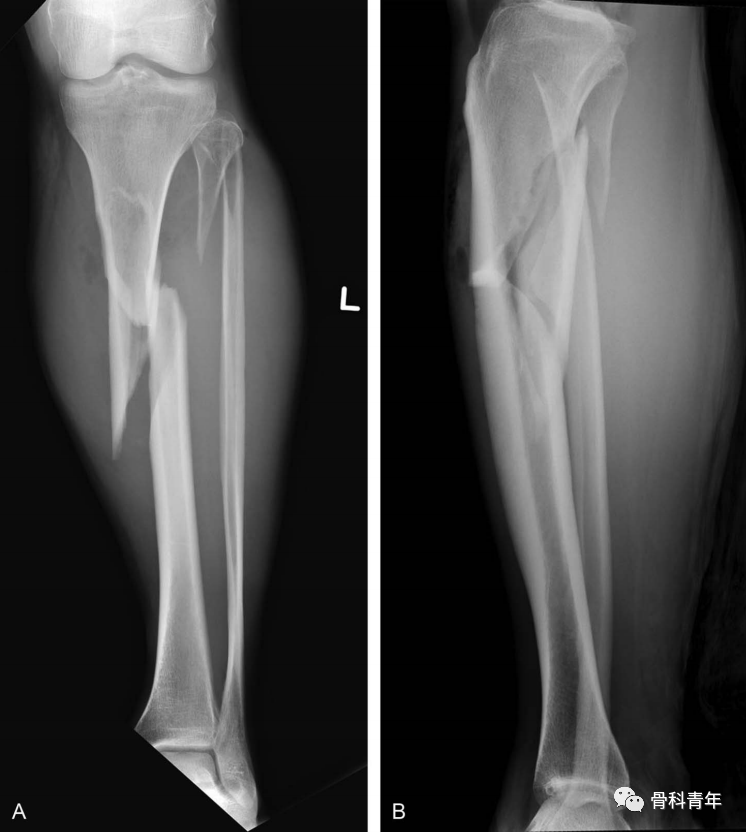

对于胫骨近端骨折,无论是髌上还是髌下入路,主钉置入后骨折成角问题不可避免,术后对线不良率依旧较高。使得部分学者坚持使用钢板固定此类型骨折。

胫骨骨折通常为高能量损伤,髓内钉治疗胫骨骨折具有创伤小、允许早期负重等优点,已逐渐成为胫骨干骨折治疗的金标准。然后对于胫骨近端骨折,无论是髌上还是髌下入路,主钉置入后骨折成角问题不可避免,术后对线不良率依旧较高。使得部分学者坚持使用钢板固定此类型骨折。

病例示例: